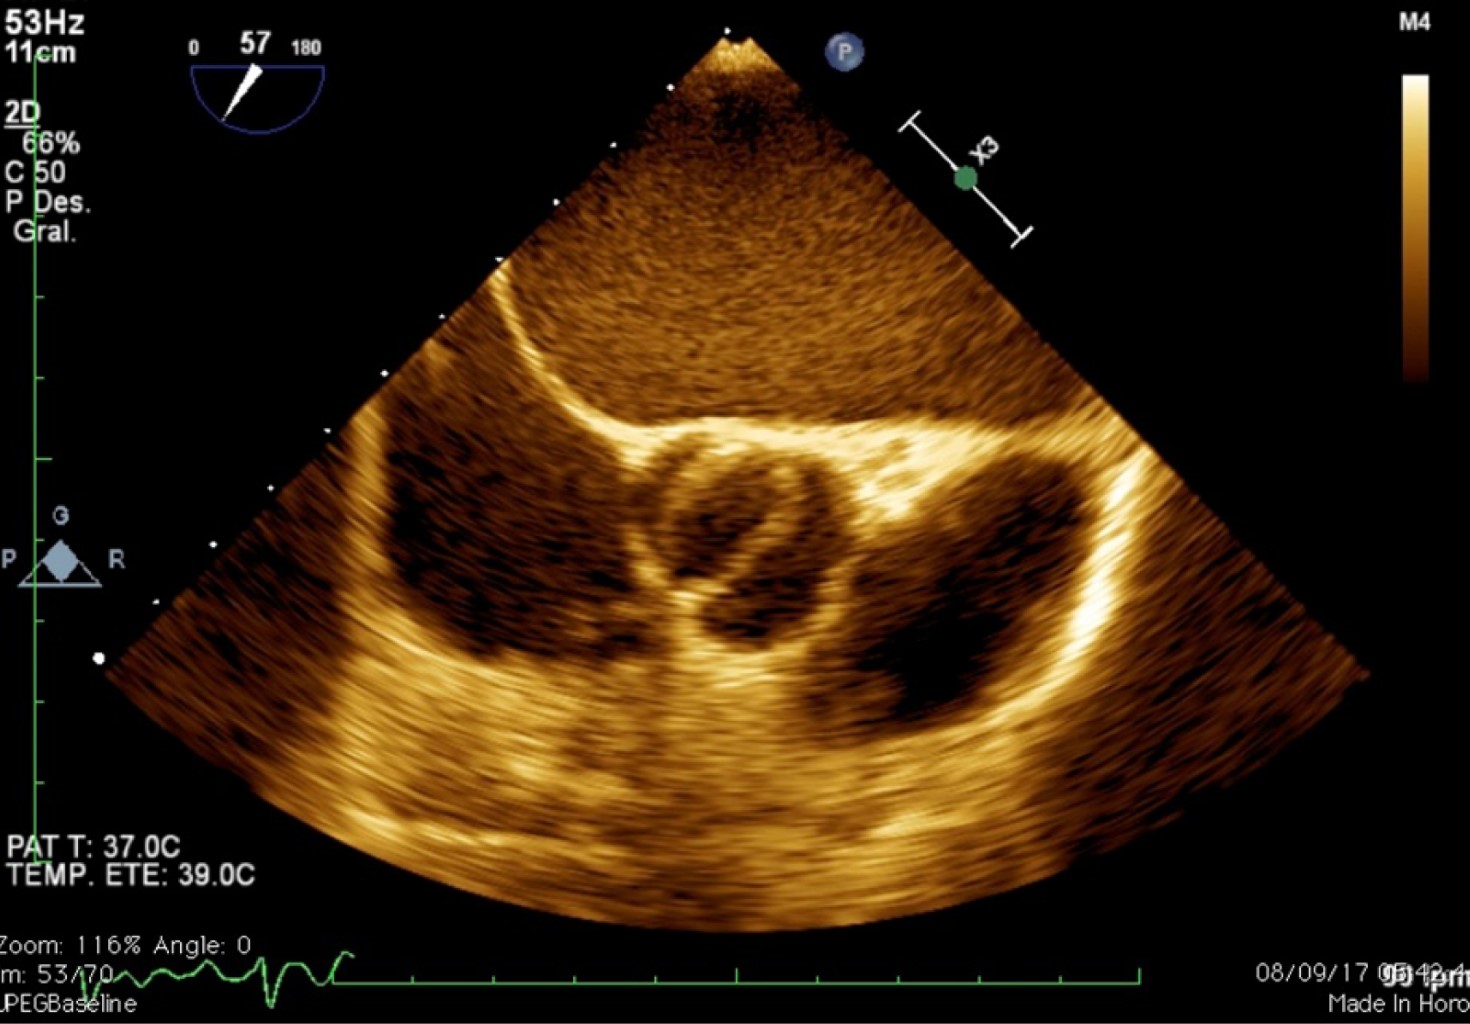

Las cardiopatías congénitas en México ocupan el segundo lugar de malformaciones congénitas en los recién nacidos, con una incidencia de 0.8-1.4%. El doble orificio de la válvula mitral (DOVM) es una cardiopatía congénita rara, con una incidencia reportada de 0.05%. Esta malformación consiste en la presentación anatómica de dos orificios mitrales comúnmente asociada a otras malformaciones congénitas como defectos septales, malformaciones completas o parciales del canal atrioventricular, coartación aórtica, tetralogía de Fallot, comunicación interauricular o interventricular, anomalía de Ebstein y persistencia del conducto arterioso. Las características clínicas son variables e incluso pueden pasar desapercibidas y ser diagnosticadas hasta la edad adulta. Se presenta el caso de una mujer joven el cual se encuentra asintomática con diagnóstico de hipertensión arterial, que durante una revisión de rutina fue diagnosticada con múltiples cardiopatías congénitas, de las cuales, su relación está poco descrita en la literatura, siendo este el tercer caso reportado. En la actualidad las técnicas de imagen multimodal permiten la mayor caracterización de las lesiones tanto de la valva como del aparato valvular, con la intención de realizar un abordaje diagnóstico y terapéutico integral para ofrecer el mayor beneficio al paciente.

Figura 2